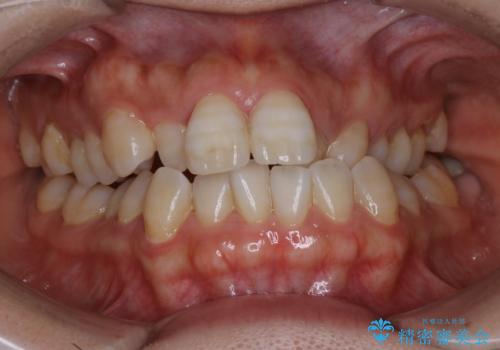

- かみ合わせ、顎のゆがみ、歯の見た目を主訴に来院された患者様です。

上の顎が下の顎に比べて小さく、それによって下の顎の位置をずらすことでしか噛めない状態でした。

また部分的に下の歯が上の歯よりも前に出てきてしまっていて、見た目にも問題がありました。